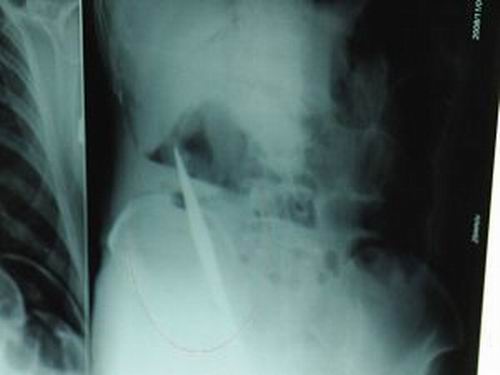

X光片上,尖刀清晰可見(jiàn)。

從男子體內(nèi)取出的尖刀足足有19厘米長(zhǎng)。

江蘇銅山一58歲男子因服毒被送到醫(yī)院搶救,可醫(yī)生采取搶救措施后卻發(fā)現(xiàn)效果不佳。后來(lái)經(jīng)細(xì)致檢查,醫(yī)生有了個(gè)驚人的發(fā)現(xiàn),該男子的體內(nèi)竟然有一把尖刀,醫(yī)生通過(guò)手術(shù)將位于其腹部右側(cè)橫結(jié)腸下緣的尖刀取了出來(lái)。這把尖刀足足有19厘米長(zhǎng)!據(jù)醫(yī)生推測(cè),這把刀應(yīng)該是從肛門(mén)推進(jìn)體內(nèi)的,不知男子為何想以如此殘酷的方式結(jié)束自己生命。由于搶救及時(shí),該男子已暫時(shí)脫離危險(xiǎn)。

昨天(11月6日)上午,記者在徐州礦務(wù)集團(tuán)總醫(yī)院重癥監(jiān)護(hù)室見(jiàn)到了這名男子,目前他雖然已經(jīng)恢復(fù)了意識(shí),但還不能開(kāi)口說(shuō)話,需要呼吸機(jī)輔助呼吸。據(jù)醫(yī)生介紹,4日中午12時(shí)左右,這名男子因服毒輕生被緊急送到醫(yī)院進(jìn)行搶救,之前,這名男子已經(jīng)在當(dāng)?shù)剜l(xiāng)鎮(zhèn)醫(yī)院進(jìn)行了近20小時(shí)的治療,但效果不佳!安∪吮晦D(zhuǎn)院到礦總院時(shí)已神志不清,血壓極低,處于休克狀態(tài)!本茸o(hù)人員給男子洗胃、初步處理以后,發(fā)現(xiàn)男子呼吸急促,于是趕緊給他拍片檢查。結(jié)果讓所有的醫(yī)生大吃一驚,竟有一把尖狀異物橫在該男子腹腔內(nèi)!當(dāng)天下午5時(shí)30分,輕生男子被推上了手術(shù)臺(tái)。經(jīng)過(guò)40多分鐘的手術(shù),該男子腹腔被打開(kāi),手術(shù)醫(yī)生發(fā)現(xiàn),男子體內(nèi)的金屬狀異物竟然是一把長(zhǎng)19厘米的尖刀!

醫(yī)生告訴記者,手術(shù)后,醫(yī)生在病人身上并未發(fā)現(xiàn)刀痕,最后,經(jīng)過(guò)檢查發(fā)現(xiàn),在該男子直腸處找到穿孔。醫(yī)生從醫(yī)學(xué)角度分析后認(rèn)為,這把尖刀應(yīng)該是從肛門(mén)插入直腸的。